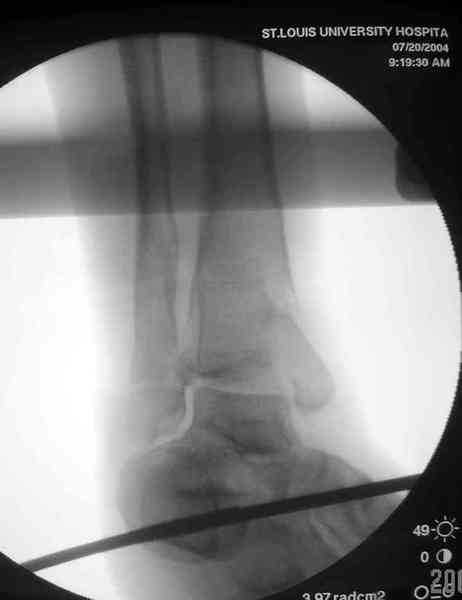

Снова приветствую вас, коллеги. К моменту вступления в обсуждение аксакалов, операция была, увы, выполнена(31.10.07.) Начали с доступа к наружной лодыжке, произвели ее фиксацию спицами, развернули кусок заднего края, наложили дистрактор, затем произвели дистракцию, фиксацию спицами дистального эпиметафиза б/бк,Рентгено-контроль. синтез наружной лодыжки 1/3пластиной. из двух коротких разрезов сформирован канал под медиальную тибиальную пластину LCP. Края ран ушиты без натяжения. Прочувствовать жесткость фиксации винтами с угловой стабильностью не удалось, поэтому дистрактор оставлен на энное время.

На представленных R-снимках не окончательный вид после остеосинтеза. Дистальная опора давила на стопу, пришлось ее сместить проксимально, в рез-те чего, она закрыла щель сустава, последние снимки не информативны.